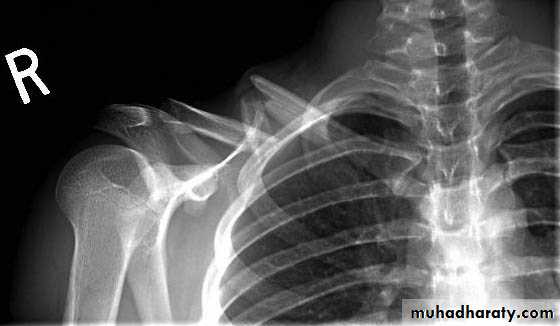

1-Fractue clavicle

2-Fracture scapula

3-The Acromioclavicular joint: